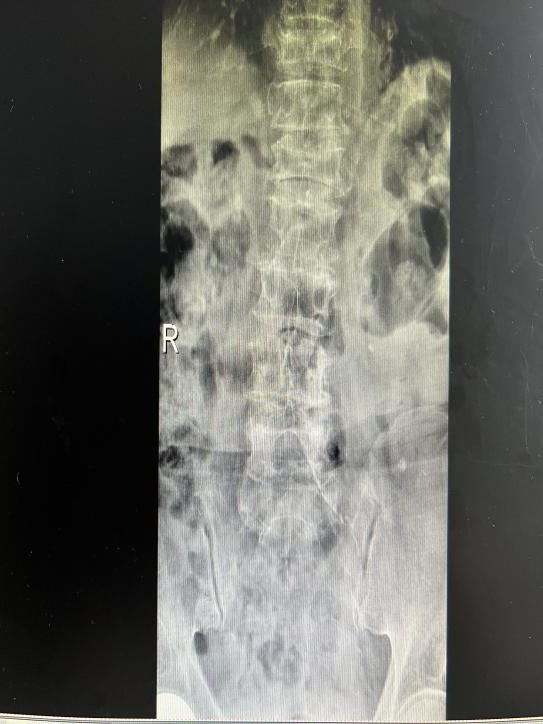

为提升区域内基层医疗机构糖尿病足诊疗服务能力、促进青年医师对糖尿病足的规范化诊治水平,遵义市第二城市医疗集团总院(贵州航天医院)圆满举办贵州省继续医学教育项目——胫骨横向骨搬移技术治疗糖尿病足专题研讨班。 贵州航天医院党委委员、副院长彭亮出席会议并致辞,遵义市第二城市医疗集团各成员单位,以及红花岗区、汇川区、绥阳县、桐梓县等多个区县的基层医疗机构骨干医师参加会议。 研讨班 本次研讨班以胫骨横向骨搬移技术在糖尿病足治疗中的应用为核心主题,围绕糖尿病药物治疗与生活方式管理策略、围手术期血糖精准调控要点、胫骨横向骨搬移技术典型病例深度解析、糖尿病足的临床分型与个体化治疗方案制定等临床实践中的热点与难点展开深入探讨,通过专题授课、案例研讨、互动交流等多元化形式,为参会者搭建了理论与实践结合的学习平台。 此次研讨班不仅为区域内基层医院搭建了学术交流与经验共享的平台,更对推动糖尿病足预防、诊断与治疗的规范化、系统化发展起到了积极作用,有效助力青年医师更新专业知识体系、提升临床技能,为进一步保障区域内糖尿病足患者的健康奠定了坚实基础。 贵州航天医院骨科专家简介 陈明勇 骨一科主任,副主任医师 临床擅长:从事创伤骨科工作约20年,对骨缺损、骨不连、骨肿瘤、肢体畸形等的肢体矫形重建及功能重建,慢性化脓性骨髓炎的根治治疗、糖尿病足的保肢治疗、快速康复理念(ERAS)下的老年骨折的诊治,四肢复杂骨折的诊治,四肢骨折等微创手术治疗具有丰富的临床经验。 2004年毕业于遵义医学院临床专业,曾在中国人民解放军总医院、广西医科大学第一附属医院、上海第六人民医院骨科进修。中国中西医结合学会骨伤科专业委员会横向骨搬移治疗糖尿病足及微血管网再生学组首届委员,遵义市医学会创伤分会常务委员。 瞿 晖 骨科党支部书记,骨二科主任,副主任医师 临床擅长:对骨科的常见病、关节外科、脊柱外科及运动医学疾病的诊治具有丰富的临床经验,熟练掌握骨科手术操作技术。 毕业于遵义医学院临床医学系,2005年前往广州中山大学第一附院骨显微医学部进修学习,2011年前往成都华西医院进修学习,并多次在省内外学习骨科相关知识,是中华医学会骨科分会会员。 赵小锋 中共党员,骨二科副主任,副主任医师 临床擅长:从事骨科临床工作11年,对骨科常见病、多发病诊疗有较为丰富的临床经验,擅长脊柱相关疾病诊断及治疗,尤其是颈、腰、腿疼痛疾病诊断及治疗,擅长胸腰椎骨折微创经皮穿刺内固定术、经皮穿刺椎体成形术、经皮穿刺脊柱内镜下腰椎间盘摘除术、单纯开创腰椎间盘摘除术、腰椎滑脱复位椎间植骨椎融合内固定术、腰椎管狭窄减压融合内固定术及人工髋、膝关节置换术等。 2012年毕业于遵义医学院外科学专业硕士研究生,2019年参加“遵义市115医学人才精英计划”于上海交通大学第一附属医院培训学习,2023年于北京大学第三人民医院脊柱外科进修学习,曾获得遵义市优秀医师荣誉称号。 遵义市手外科第一届委员,遵义市医学会创伤分会第一届委员,遵义市医学会创伤分会第二届委员,贵州省康复医学会第三届脊柱脊髓专业会委员,遵义市医学会烧伤与整形外科学分会委员,发表论文5篇,其中国家级核心期刊1篇,SCI论文1篇,主持市级课题1项并结题,参与市级课题2项。 赵兴东 骨科主任医师 临床擅长:擅长骨科的常见病及各种创伤、四肢骨折创伤修复、骨感染、手足疾病的诊治和手足体表畸形的矫形整复,熟练掌握骨科四肢骨病及创伤的手术操作技术,尤其在四肢关节复杂性损伤、手足外伤、组织缺损创面、难治创面的皮瓣修复方面及平足、高弓足矫形方面及四肢慢性疼痛诊治、康复方面具有丰富的临床经验。 硕士研究生,毕业于遵义医学院临床外科系,2015年前往山东省立医院手足外科进修学习;遵义市医学分会创伤分会第一、二届委员,遵义市手外科医学会第二委届员会常务委员;在省级及省级以上期刊发表文章9篇,参编著作2部,参与主持并完成市级课题1项,参与市级课题2项、省级课题1项。 张艳金 中共党员,骨科副主任医师 临床擅长:从事骨外科工作16年,对复合伤、多发伤的救治、四肢骨干骨折、关节周围骨折、骨肿瘤、骨髓炎等诊治具有丰富的临床经验。 中共党员,硕士研究生,2006年本科毕业于山西医科大学第二临床医学院,2011年研究生毕业于北京军区总医院;在“老年COPD患者合并髋部骨折的诊治”国际合作课题组研究两年,在老年髋部骨折的诊治方面具有丰富的经验,并发表论文6篇;主持遵义市级课题1项,承担遵义医科大学的临床教学工作,获得遵义医科大学优秀带教老师荣誉。编撰有《骨科疾病诊疗精粹》一书,开展2项新技术,编撰地方规范《务川自治县创伤骨科常见疾病诊疗规范》一书。 张俊凯 骨科副主任医师 临床擅长:从事骨科临床工作28年,对创伤骨折、骨感染、骨缺损、骨不连等外科诊治,四肢骨折的微创手术治疗,四肢复杂骨折(如关节内粉碎性骨折、多发骨折等)的损伤控制及手术治疗等具有丰富的临床经验。 1995年毕业于遵义医学院临床专业,2009年前往复旦大学附属医院骨科进修1年。 卢懿明 中共党员,骨科副主任医师 临床擅长:从事骨科工作18年,对创伤骨折、四肢骨折的微创手术治疗、四肢复杂骨折(如关节内粉碎性骨折、多发骨折等)的损伤控制及手术治疗,尤其是髋部骨折的PFNA等微创技术,踝关节骨折、膝关节周围骨折的Mipo微创技术等具有丰富的临床经验,开展了4项新技术,发明6项新型专利技术。 2005年毕业于遵义医学院临床专业,2017年,前往南方医科大学第三附属医院骨科进修半年,回院后运用Mipo技术对骨干骨折及干骺端骨折的治疗技术,同时积极开展骨盆骨折、髋臼骨折腹直肌外侧切口的应用;发表了多篇专业论文,经常参与省内外学术交流会授课,获得医院荣誉称号多个。 邬夏荣 骨科副主任医师 临床擅长:从事骨科工作16年,对四肢复杂骨折、骨肿瘤的诊治,尤其是足踝创伤、慢性踝关节损伤、平足症等诊疗具有丰富的临床经验。 2006年毕业于遵义医科大学临床医学专业,曾在陆军军医大学西南医院进修学习,发表多篇骨科学术论文。 余德怀 中共党员,骨科副主任医师 临床擅长:从事骨科工作10余年,对运动医学、骨关节、脊柱外科常见病、多发病的诊治具有丰富的临床经验。 硕士研究生,2011年毕业于遵义医学院临床医学专业,曾前往遵义医科大学附属医院运动医学专业进修学习;是贵州省医学会运动医学分会青年委员,西部关节镜联盟委员;发表多篇骨科学术论文。 冯 乾 骨科副主任医师 临床擅长:从事骨科工作近20年,熟练掌握骨科多发病及常见病的诊治,尤其对脊柱退变性疾病的诊断及治疗具有丰富的临床经验,主要研究脊柱微创相关治疗方式,能熟练开展椎间孔镜及UBE。 曾前往北京大学第三医院进修学习疼痛及椎间孔镜、首都医科大学友谊医院专业进修脊柱内镜;是贵州省康复医学会第三届脊柱脊髓专业委员会委员;发明专利3项、发表脊柱外科专业论文多篇。 贵州航天医院骨科简介 基本情况 贵州航天医院(原3417医院)骨科组建于1968年,前身是以创伤和断肢(断指)再植闻名于世的上海市第六人民医院骨科,中国断肢(断指)再植的奠基者、中科院院士陈仲伟等专家莅临科室指导医疗和教学,并在70年代开展了贵州省首例断肢(断指)再植手术。组建50余年来,诊治患者已逾百万,挽救了无数的伤病员,成为了保障遵义地区人民群众健康的重要支撑。 经过几代人的不懈努力,今天的骨科,已由创伤骨科发展至骨病、骨肿瘤、骨结核等领域,现有脊柱外科、关节外科、四肢创伤、手足外科四个亚专科,成为了集医疗、教学、科研于一体的综合学科,是贵州省临床重点专科、遵义市临床重点专科、遵义市骨科临床医学中心、遵义市基层骨科专科联盟理事长单位。 科室目前开放床位110张,共有医护人员50余人,副高级以上专家18人,硕士研究生15人。拥有一流骨科医疗设备多台,每年不定期选派优秀技术骨干到全国各大知名医学院校进修、学习、参观、交流,并邀请国内、国外知名专家教授来院进行交流、指导,通过不断引进国内外先进的诊疗技术,科室医疗技术水平稳步提升,为广大人民群众提供了优质的医疗服务。 专科特色 骨一科 (一)骨缺损、骨不连的肢体与功能重建 胫骨横向骨搬移技术治疗糖尿病足: (二)慢性骨髓炎的根治治疗 (三)肢体缺血性疾病如糖尿病足、脉管炎的保肢治疗 (四)皮瓣修复 (五)复杂创伤的治疗 (六)老年髋部骨折及小儿骨折快速手术 老年髋部骨折: 骨二科 (一)胸腰椎骨折微创经皮椎弓根螺钉固定术 (二)老年性骨质疏松性患者腰椎滑脱脊柱内固定术(骨水泥螺钉) (三)V形双通道脊柱内镜技术(VBE)腰椎融合术治疗腰椎退行性疾病 (四)老年性骨质疏松性骨折(PVP/PKP)术 (五)人工髋关节置换术 (六)双侧股骨头坏死人工全髋关节置换 (七)右侧全髋置换术后假体周围骨折翻修 (八)人工膝关节置换术 (九)人工膝关节假体松动翻修 (十)关节镜技术 传统手术切口 关节镜技术切口 诊疗范围 骨一科 1.四肢创伤、矫形。 2.手、足踝外科。 骨二科 End